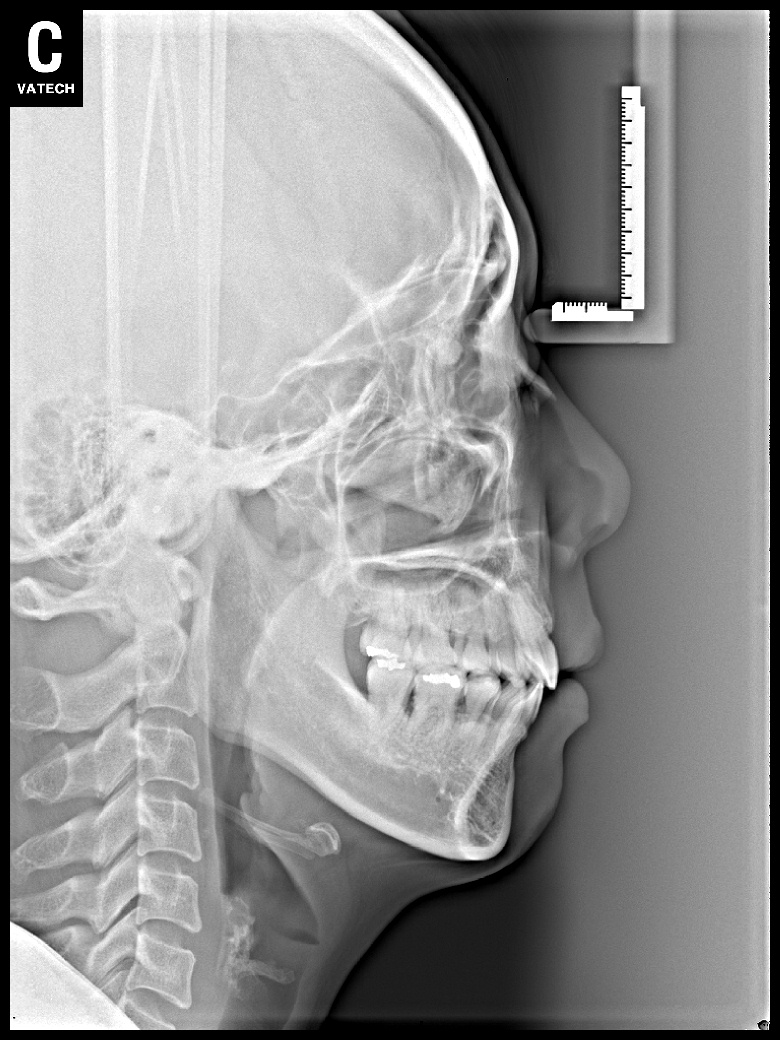

치료 후 사진입니다.